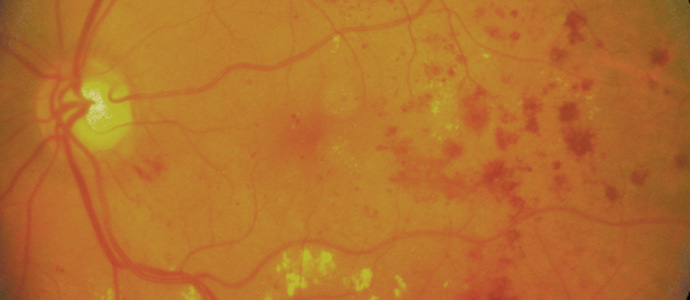

중심망막정맥폐쇄

중심 정맥이 막히면 혈액이 빠져나가지 못해 망막 안에서 정체되며,

정체된 혈액이 주변 정맥에 압력을 가하게 됩니다.

압력을 견디지 못한 정맥이 터지면서

망막 전반에 출혈과 부종이 발생하는 질환입니다.